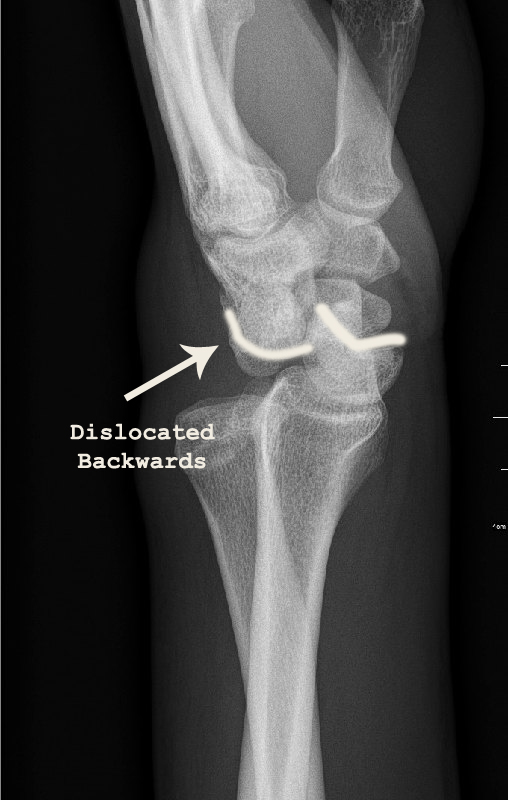

X-rays of his left wrist showed a fracture through the scaphoid bone of the wrist together with dislocation of the lunate bone. The diagnosis was a trans-scaphoid peri-lunate fracture dislocation.

Due to the dislocation of his left wrist, the nerve in the front of the wrist (median nerve) was being compressed and it was causing him numbness of the left hand.

There dislocation was immediately reduced under sedation and with fluroscopic confirmation.